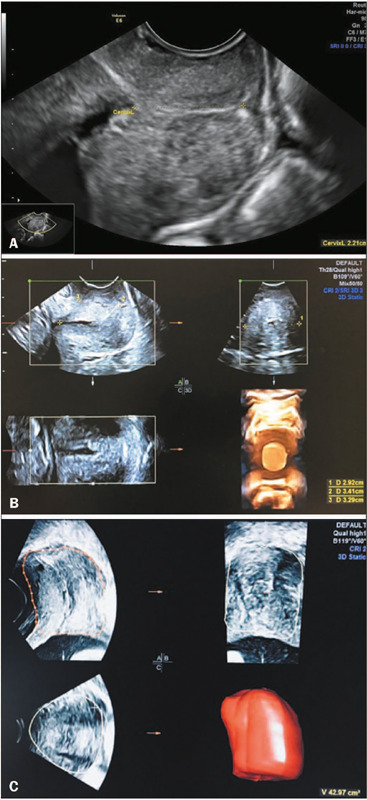

Objective: The purpose of this study was to evaluate the agreement between and reproducibility of specific two-dimensional (2D) and three-dimensional (3D) ultrasound methods in assessing cervical volume in pregnant women in their second trimester.

Materials and methods: This was a prospective cross-sectional study of 48 asymptomatic pregnant women at 20-24 weeks of gestation. All cervical volumes were determined by transvaginal ultrasound, with a 2D method employing a geometric formula {π * [(anteroposterior diameter + transverse diameter) * ¼] * length}, where π = 3.14, and a 3D method employing a virtual organ computer-aided analysis. Intraobserver and interobserver reliability was analyzed by calculating the intraclass correlation coefficient (ICC).

Results: The mean maternal age and timing of the ultrasound examination were 26 ± 6 years and 21 ± 1 weeks of gestation, respectively. The mean cervical volumes measured by the 2D and 3D ultrasound methods were 27.71 ± 9.27 cm3 and 35.21 ± 8.85 cm3, respectively. Cervical length and volume showed a positive correlation with both methods-r = 0.77 (p < 0.001) and r = 0.70 (p < 0.001), respectively. Intraobserver reliability was excellent for both methods, with ICCs of 0.92 and 0.93 for the 2D and 3D methods, respectively. Interobserver reliability was good (ICC: 0.81) for the 3D method, whereas it was poor (ICC: 0.37) for the 2D method. Reproducibility of the transverse diameter measurement was low, with an intraobserver ICC of 0.41 and an interobserver ICC of 0.48.

Conclusion: Cervical volume measurements obtained with 2D and 3D ultrasound methods seem to show satisfactory agreement and good intraobserver reliability. In our study sample, the 2D ultrasound method showed low interobserver reliability, whereas the 3D ultrasound method was more reliable, with good intraobserver and interobserver reliability.